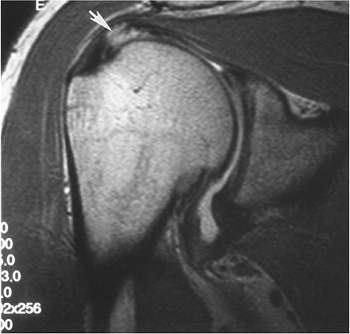

FIGURE 7-19 Coronal MR arthrogram image of a moderate-sized full-thickness rotator cuff tear with retraction (arrow).